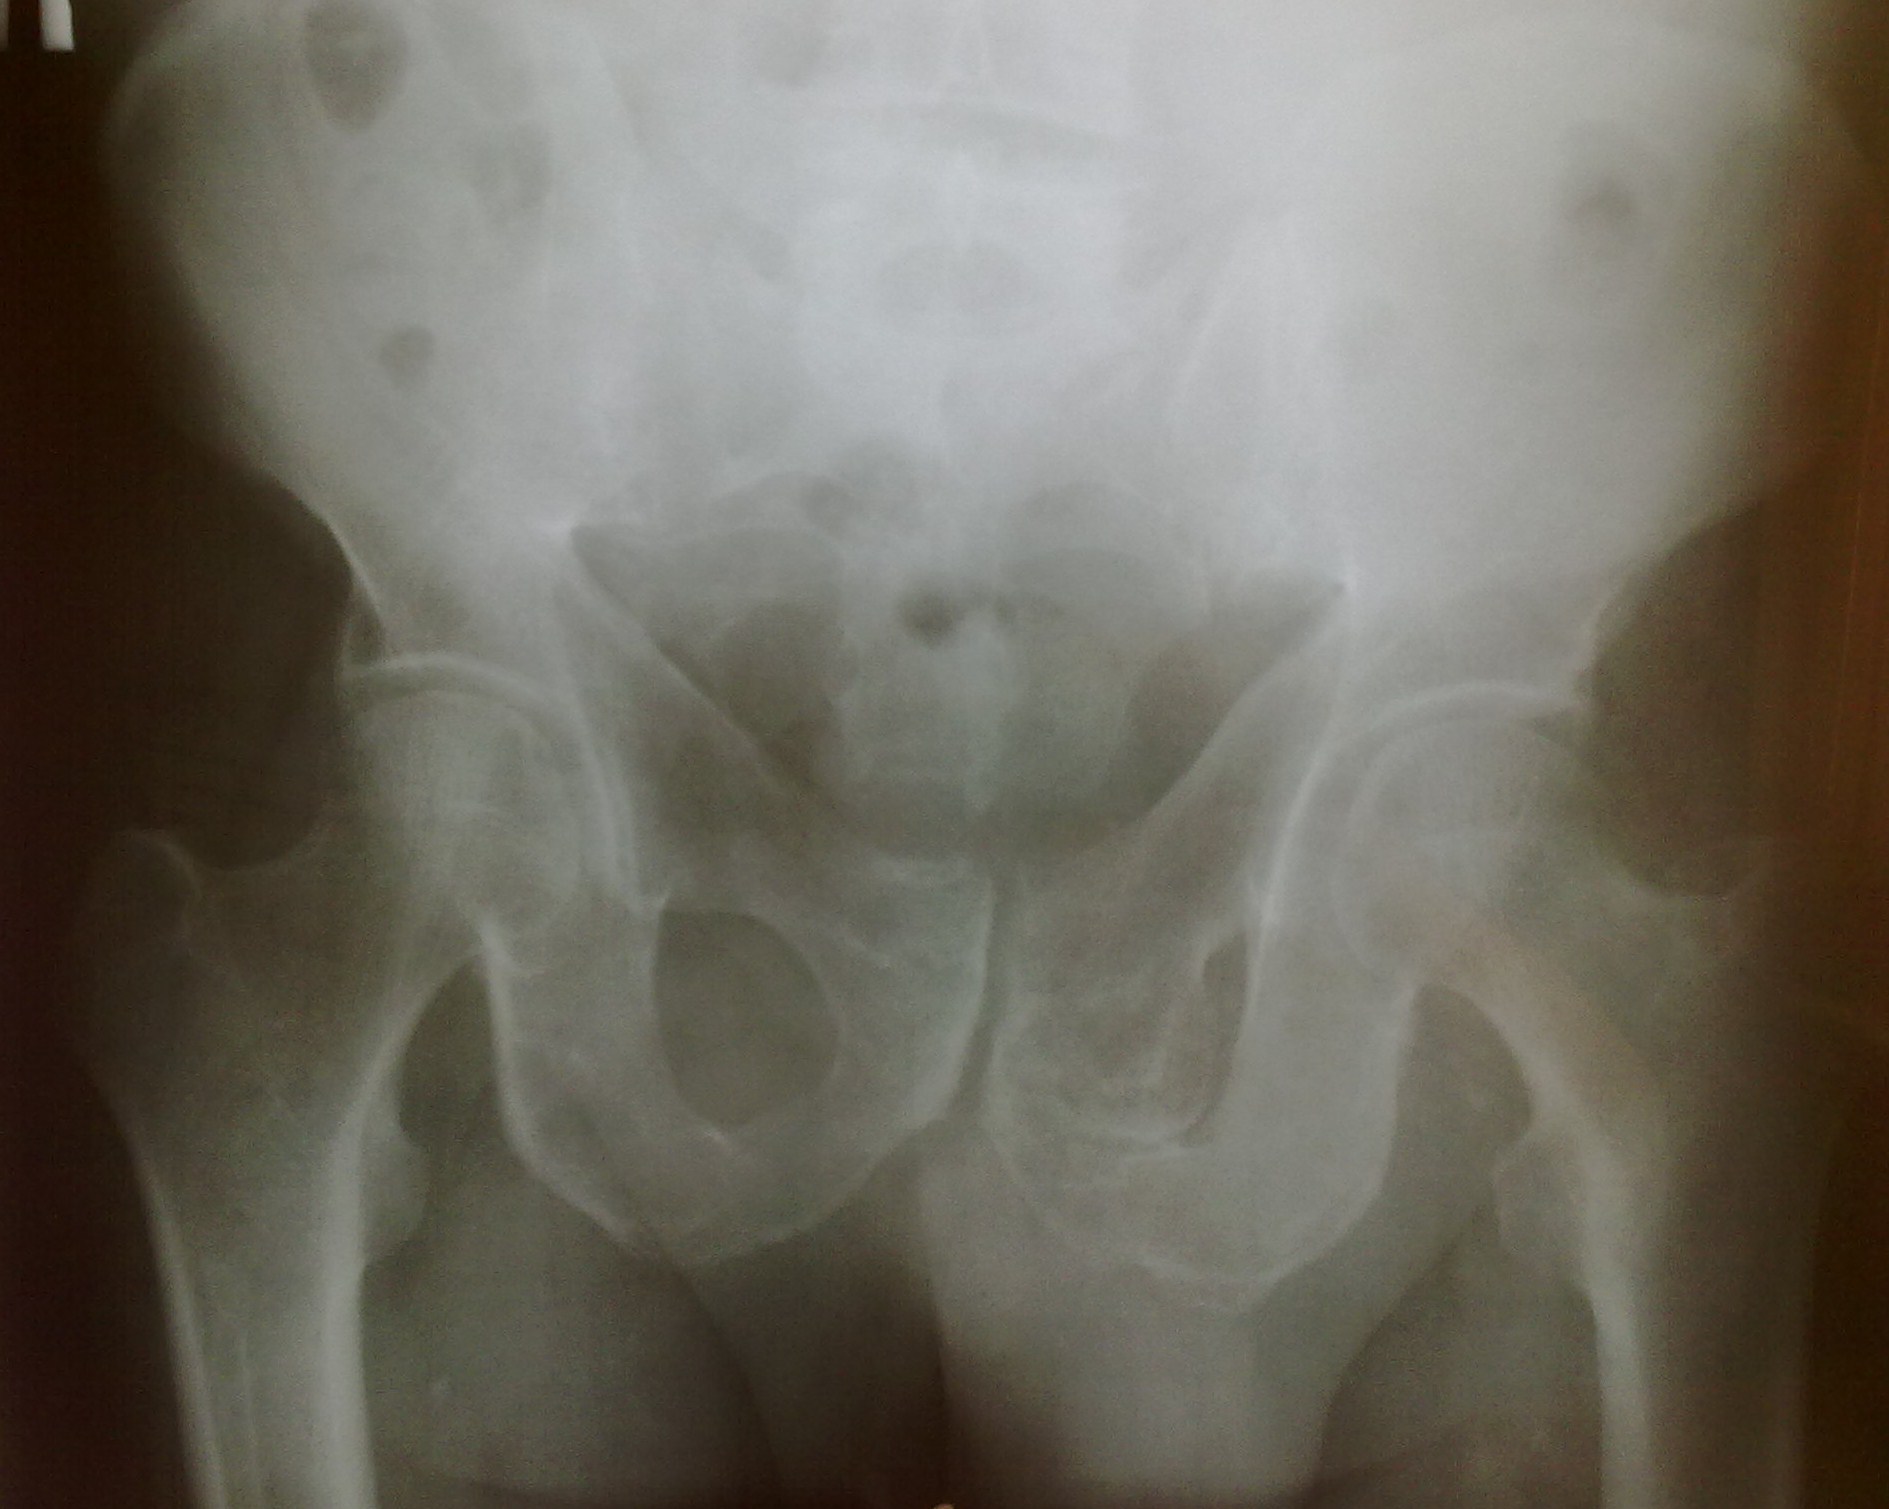

Мужчина с жалобами на боль в левом тазобедренном суставе. Написала остеому ( остеохондрому под вопросом), порекомендовала КТ. Что еще можно в дифф.ряд поставить? https://radiomed.ru/sites/default/files/styles/case_slider_image/public/user/5662/taz_pric.jpg?itok=hHLuq8Ds https://radiomed.ru/sites/default/files/styles/case_slider_image/public/user/5662/taz_pric1.jpg?itok=zbU7U7XJ ID:48793 Fri, 21/06/2013 - 05:15 #1 Vikkur Offline Last seen: 4 years 7 months ago Joined: 24.09.2009 - 14:34 Posts: 1749 как то больше аномалию развития напоминает, а травмы данной области были?Приложения: Виктор. Fri, 21/06/2013 - 07:00 #2 Helios Offline Last seen: 7 months 2 weeks ago Joined: 06.08.2010 - 15:16 Posts: 4417 Говорит, что не было. Fri, 21/06/2013 - 10:51 #3 Almo Offline Last seen: 1 day 11 hours ago Joined: 28.09.2008 - 18:50 Posts: 8248 как то больше аномалию развития напоминает ------------------------------------------------------------------------------------------------------------------------------- +1.Хочется думать , что это либо диспластические проявления, либо посттраматическая деформация ( возможно не помнит, потому, что в раннем детстве- но, это только предположение ). Fri, 21/06/2013 - 20:30 #4 Алексей Игореви... Offline Last seen: 6 years 10 months ago Joined: 08.08.2012 - 21:52 Posts: 786 Больше склоняюсь к остеохондродисплазии. Структура ткани вроде бы однородная. По плотности одинаковая с правой стороной. Хотя все может быть. "Обучая других - учишься сам". Н.И.Пирогов Fri, 21/06/2013 - 22:05 #5 Катенёв Валенти... Offline Last seen: 7 years 2 weeks ago Joined: 22.03.2008 - 22:15 Posts: 54876 По всей видимости в дифряду должно быть учтено... Остеома 1.aa_.1.ko_..slayd2_.jpg54.99 кб2.aa_.2.ko_..slayd12.jpg117.75 кб3.aa_.3.ko_..slayd14.jpg149.69 кб4.aa_.4.ko_..slayd15.jpg82.01 кб5.aa_.5.ko_..slayd16.jpg139.24 кб6.aa_.6.ko_..slayd18.jpg163.46 кб7.aa_.7.ko_..slayd19.jpg168.98 кб Sat, 22/06/2013 - 04:36 #6 Helios Offline Last seen: 7 months 2 weeks ago Joined: 06.08.2010 - 15:16 Posts: 4417 Спасибо за мнения. Sun, 23/06/2013 - 00:17 #7 tatyana Offline Last seen: 4 years 1 month ago Joined: 24.06.2009 - 08:33 Posts: 2090 Лен, все верно сделала, это остеохондрома "самоуверенность дилетантов - предмет зависти профессионалов" Sun, 23/06/2013 - 02:24 #8 Helios Offline Last seen: 7 months 2 weeks ago Joined: 06.08.2010 - 15:16 Posts: 4417 Татьяна, спасибо!Я чувствовала, что это она и есть!

как то больше аномалию развития напоминает, а травмы данной области были?

Говорит, что не было.

+1.Хочется думать , что это либо диспластические проявления, либо посттраматическая деформация ( возможно не помнит, потому, что в раннем детстве- но, это только предположение ).

Больше склоняюсь к остеохондродисплазии. Структура ткани вроде бы однородная. По плотности одинаковая с правой стороной. Хотя все может быть.

По всей видимости в дифряду должно быть учтено...

Остеома

Лен, все верно сделала, это остеохондрома

Татьяна, спасибо!Я чувствовала, что это она и есть!